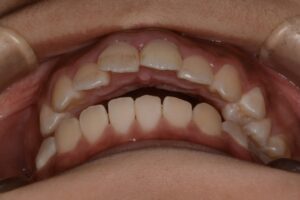

初診時:前歯を転んでぶつけてしまった。歯並びも気になるとのことで来院。

下からあおった写真だと前歯が咬んでいない。このままだと臼歯部に過度な負担がかかり歯を割ってしまう力がかかる。